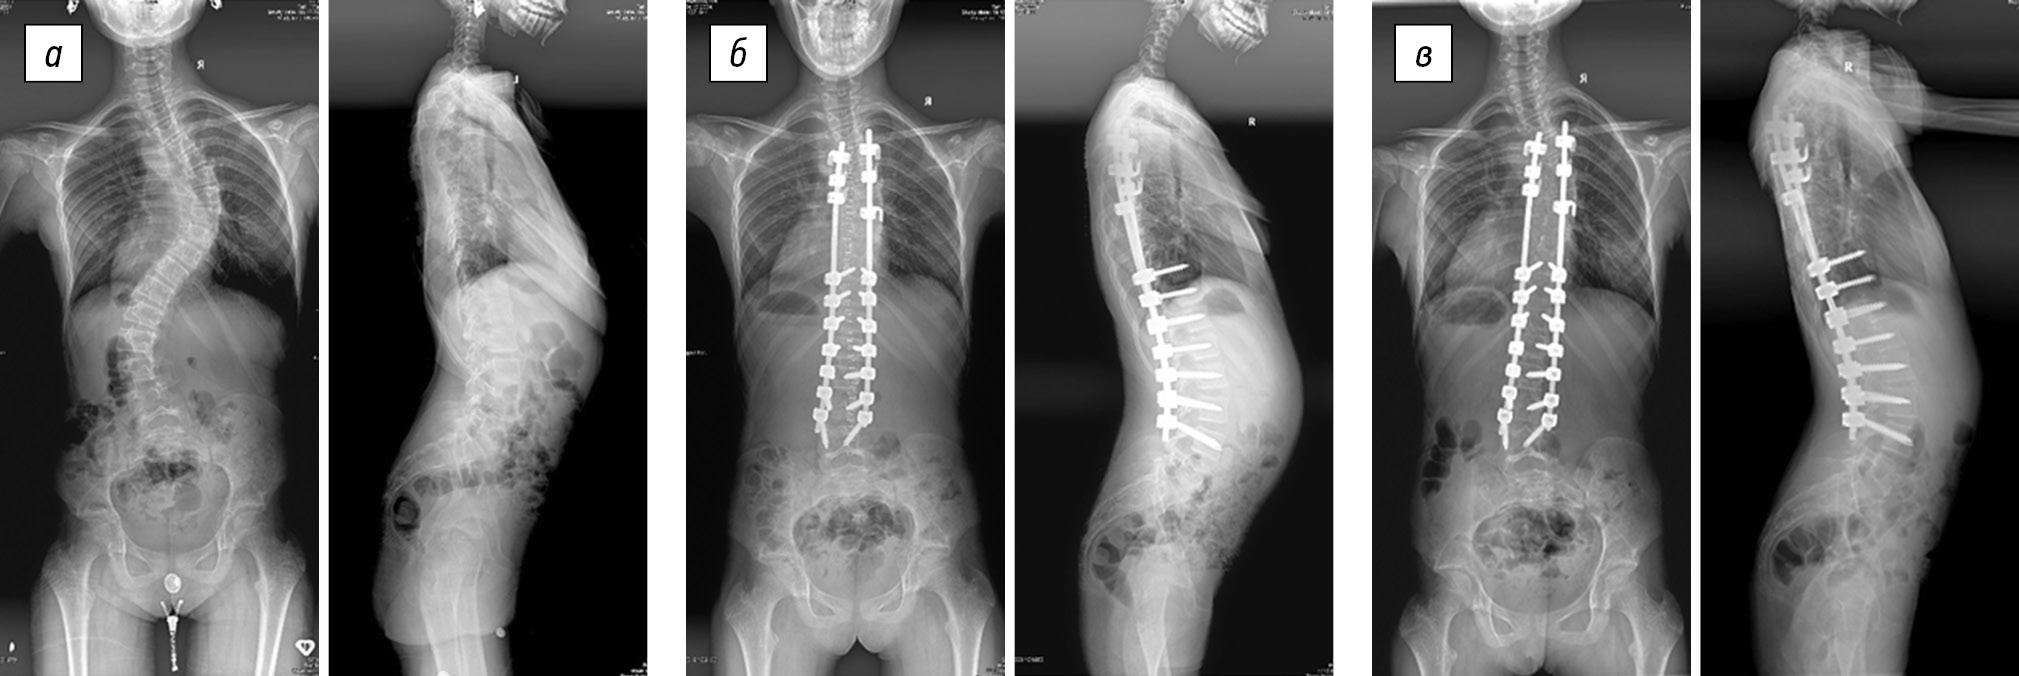

In group 3 (Table 3), the preoperative size of the thoracic scoliotic curve was 68.9 ± 20.3°, and the postoperative thoracic scoliotic curve was reduced to 16.1 ± 11.5° (p < 0.05). The value of the primary correction was 52.8 ± 12.4°, which was found in 78.2 ± 10.1% of the cases (p < 0.05). There was no postoperative progression in the immediate postoperative period and at the end of the follow-up period (Fig. 3). The average patient age was 12.9 ± 1.1 years, and the average duration of postoperative follow-up was 28.1 ± 16.7 months.

Fig. 3. Radiographs of a 10-year-old female patient in two views: a — preoperative image of degree IV scoliotic deformity (50° according to Cobb) with equivalent right-sided thoracic and left-sided lumbar curves, thoracic kyphosis of 29°, and lumbar lordosis of 57°; b — surgical correction of scoliotic deformity of the spine using total transpedicular fixation without ventral intervention results in main thoracic curve of 11°, lumbar anti-curvature of 8°, thoracic kyphosis of 19°, and lumbar lordosis of 45°; c — X-ray control 6 years after the surgery revealed the main thoracic curve of 11°, lumbar anti-curvature of 8°, thoracic kyphosis of 19°, and lumbar lordosis of 57°